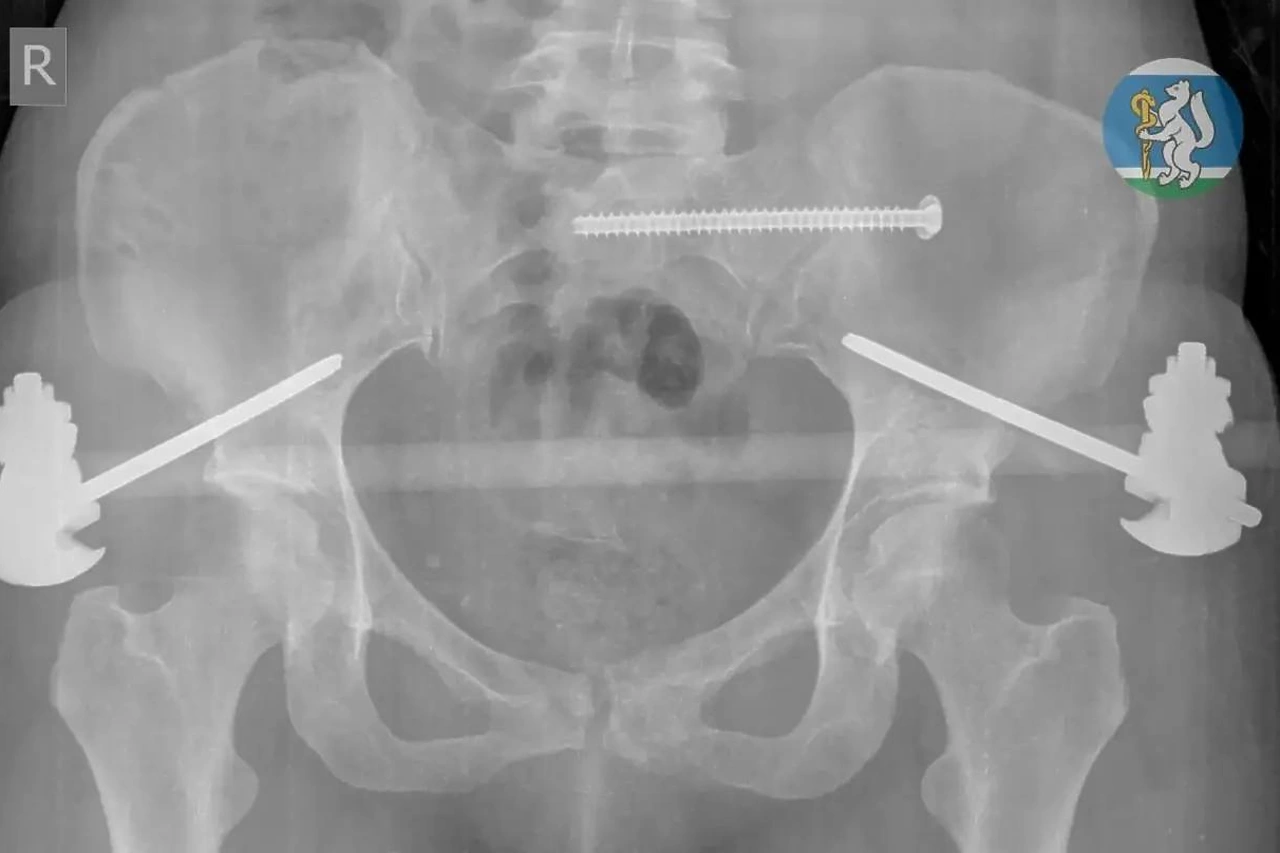

У пострадавшей диагностировали черепно-мозговую травму, повреждение позвоночника, переломы таза и ноги, а также травмы грудной клетки и лёгких. Врачи экстренно вывели её из шока, остановили кровотечение и провели сложную операцию.

После этого женщина находилась в реанимации на ИВЛ, затем перенесла ещё одно вмешательство. Благодаря поэтапному лечению и ранней реабилитации она снова начала двигаться. Спустя месяц пациентку выписали, сейчас она проходит восстановление.